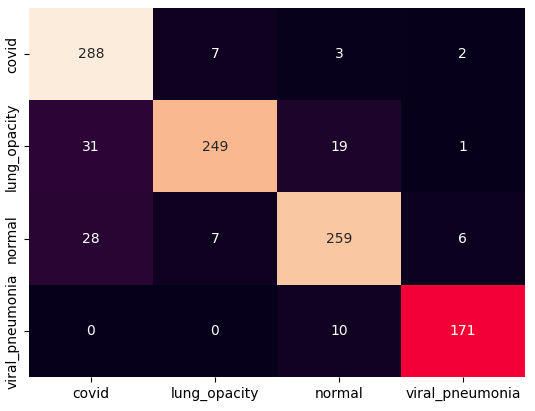

The training procedure in all scenarios has converged. Looking at the evolution of training and validation accuracy (Fig. 11a) indicates that a larger validation dataset would be beneficial. To stabilise the classifier training a procedure of multiple training runs to select the best model is used (Materials and methods). Resulting classifiers are able to discriminate between classes with good precision, for example, see the confusion matrix of the best overall model presented in Fig. 11b. It can also be seen that for the normal class, the rate of misclassified images as COVID-19 ones is higher than for other classes. This effect is present for all models although smaller for the ones based on the EfficientNet-B0 architecture. In addition, the EfficientNet-B0 variants excel if the correct classification of viral pneumonia class images with the smallest rate of errors. However, the EfficientNet-B0 GAN augmentation scenario shows increased misclassification of healthy images which leads to a poor performance. The evolution of the training accuracy as well as confusion matrices for all models are summarised at the end of this section.

Training results for the two architectures are summarised in Figs. 13, 14, 15, 16, and Table 3. For each architecture four scenarios are considered as described in Training process part of the Materials and methods Section.